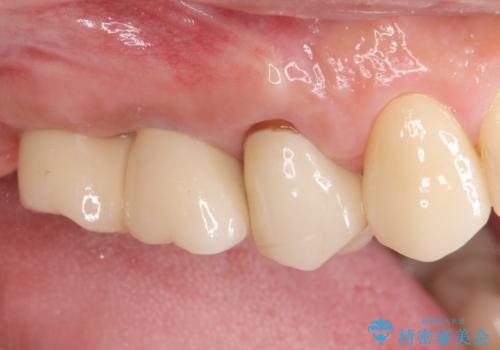

挺出歯を圧下してスペースを確保!目立たない部分矯正で下顎大臼歯にインプラント治療を実現